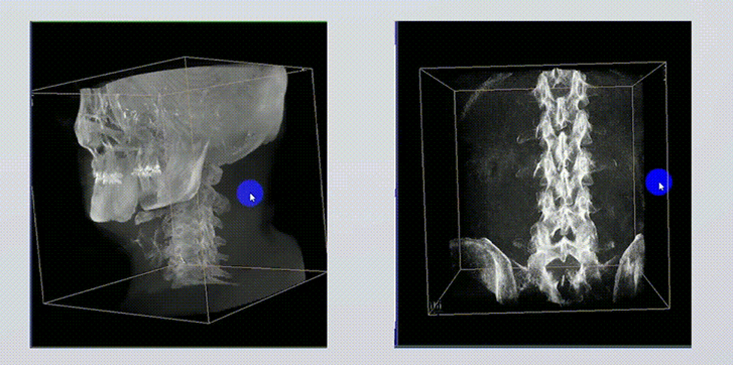

二、三維成像實(shí)時(shí)監(jiān)控

1、術(shù)中實(shí)時(shí)三維成像

術(shù)中三維成像和橫斷面圖像提供多角度的手術(shù)診斷信息,輔助醫(yī)生進(jìn)行術(shù)中評(píng)估判斷,諸如骨折復(fù)位情況和內(nèi)植入螺釘?shù)某叽绾臀恢?,輔助手術(shù)更好地完成。

2、三維成像視野大

提供更大的術(shù)中三維成像視野,采集更多圖像信息,可一次拍全全段頸椎、全段腰椎、七節(jié)胸椎、雙側(cè)骶髂關(guān)節(jié)、股骨頭及單側(cè)盆骨。